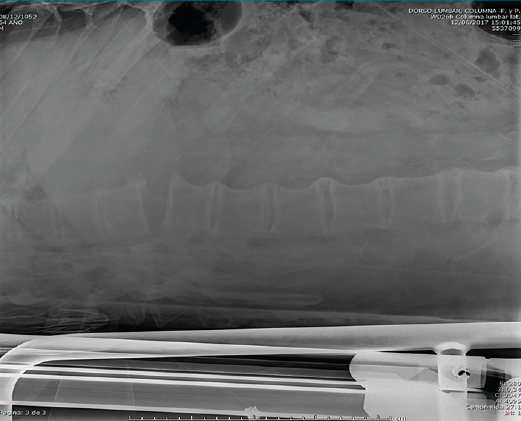

En la Figura 1 se muestra la primera radiografía que le realizan en el centro hospitalario más cercano al accidente. En ella visualizamos un perfil dorsolumbar realizado sobre la camilla de transporte con 2 imágenes. Por un lado, una apertura anterior patológica a través de disco a nivel dorsal, concretamente T10/T11. También observamos una sindesmofitosis de todo el raquis que conocemos como “caña de bambú”. Esto orienta a una enfermedad reumática, concretamente una espondiloartitis anquilosante(1).

Figura 1. Radiografía inicial.